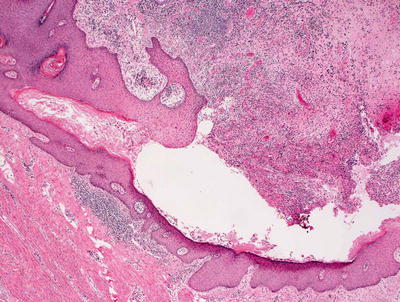

The histologic findings in acne conglobata are shared with those seen in other conditions including hidradenitis suppurativa. There is marked follicular plugging resulting in multiple follicular cysts that can be quite large (Fig. 10.9). These cysts are surrounded by dense inflammation including lymphocytes, neutrophils, and often granulomas with abundant multinucleated giant cells. As a result of repeated rupture of follicular cysts, there is extensive dermal scarring and even sinus tract formation (Fig. 10.10).

Fig. 10.9

Acne conglobata shows marked distortion of pilosebaceous units with dense scar formation

Fig. 10.10

Abundant pilosebaceous units are disrupted and surrounded by dense scarring throughout the dermis in acne conglobata